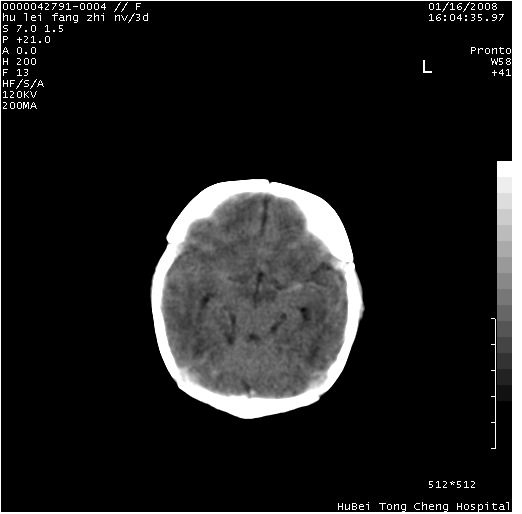

患儿 女,3天。惊跳,纳差。第二胎顺产,羊水ⅱ度。

临床诊断:hie?

颅脑ct轴位平扫(层厚、层距均为7mm),图像如下:

hie合并蛛网膜下腔出血

hie合并蛛网膜下腔出血,五、六脑室形成。

支持hie伴少量蛛血.